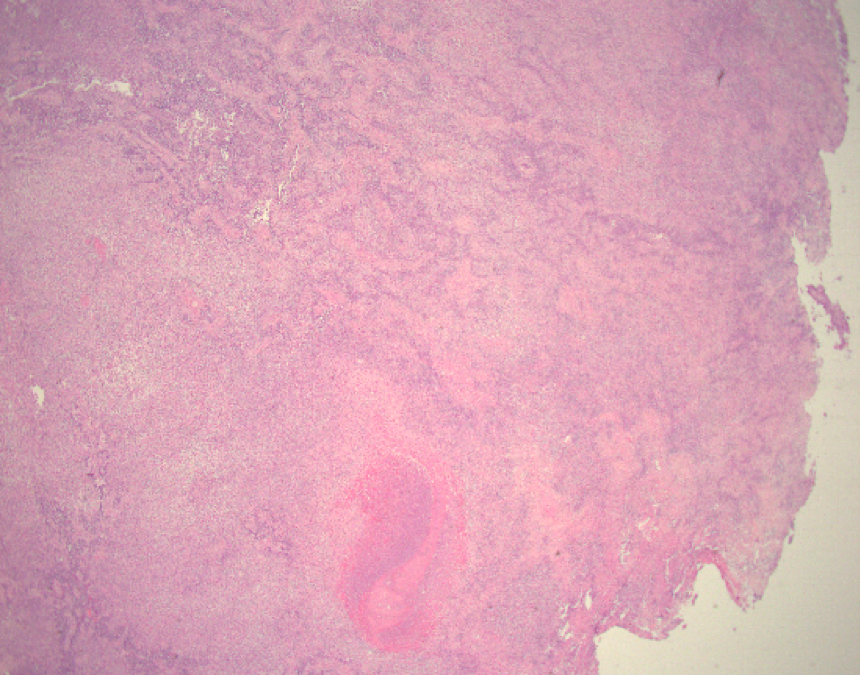

Patient is a 68-year-old female with a about 20 cm ovary mass. The mass has a mixed (solid/cystic) cut surface.

This is an adult granulosa cell tumor with areas of edema, necrosis, and calcification. A reticulin stain reveals diminished fibers, encompassing groups of tumor cells. Tumor cells are positive for SF-1 and inhibin, rare cells positive for calretinin, and negative for EMA, and CK7. The morphologic features, special stains, and immunophenotype are those of an adult-type granulosa cell tumor. Small cell carcinoma often has a much high mitotic figure rate, lack of cytological features of AGCT, and inhibin-. AGCT may be occasionally difficult to distinguish from fibromas or fibrosarcomas. Reticulum stains often show abundant intercellular fibrils in these tumors.